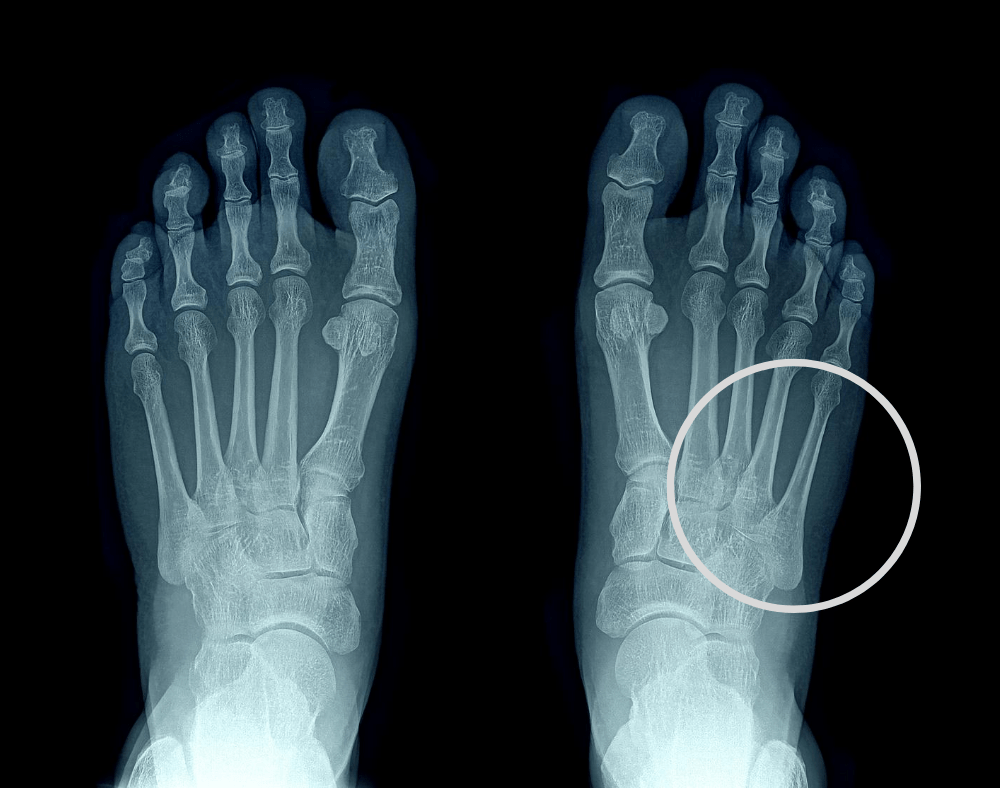

Foot Jones Fracture A jones fracture is a fracture that occurs at the base of the fifth metatarsal bone (the long bone on the outside of the foot that leads up to the pinky toe.). This bone is on the middle outside of your foot,. Jones fractures are characterized by bruising, swelling, pain, and an inability to walk. What is a jones fracture? A jones fracture is a fracture that occurs at the base of the fifth metatarsal bone (the long bone on the outside of the foot that leads up to the pinky toe.). A jones fracture is a fracture of the bone on the outside of the foot. Jones fractures are caused when you put sudden force on the outside of your foot with your foot twisted away from your body. If you fracture the fifth metatarsal bone in your foot, it is called a jones fracture.